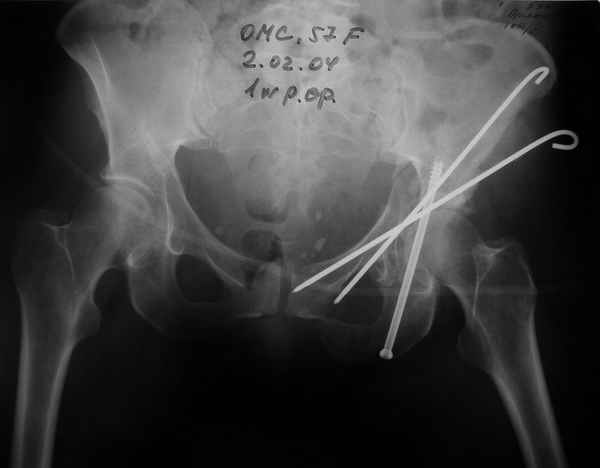

Уважаемые коллеги,Мужчина 36 лет от роду попал в ДТП 24.08.04 Рентгенограммы в приложении.

Диагноз- перелом с вовлечением таза, разрыв правого сакро-илиак сочленения vertical shear injury, перелом крыла подвздошной кости?, перелом ацетабулум Т type или Both column?, перелом шейки бедра, перелом проксимального отдела бедра.

перелом крыла правой подвздошной кости, перелом обеих колонн вертлужной впадины, двусторонний перелом лонных костей (С2.2) повреждение передних связок правого крестцово-подвздошного сочленения,

ипсилатеральный перелом шейки и диафиза бедра.